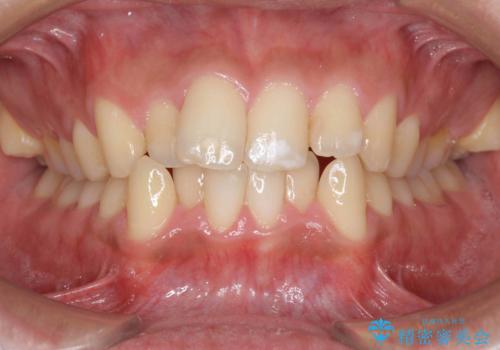

ワイヤーによる全体的ながたつきの矯正治療